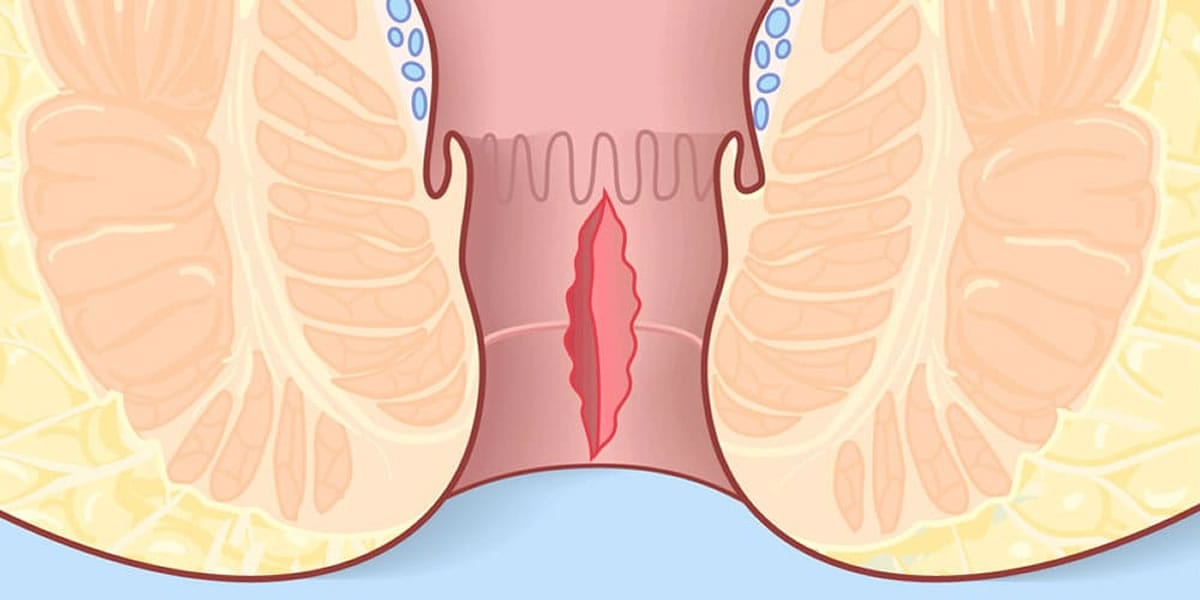

شقاق چیست ؟ چه علائمی دارد؟

شقاق مقعدی به پارگی یا زخم در بافت نازک مقعد اطلاق میشود که میتواند به دلیل عواملی مانند یبوست، زایمان، یا رابطه جنسی ایجاد شود. این مشکل معمولاً با درد شدید، خونریزی، و ناراحتی همراه است. تشخیص صحیح شقاق مقعدی از اهمیت بالایی برخوردار است تا بتوان درمان مناسب را انجام داد.

چه علائمی نشاندهنده شقاق مقعدی هستند؟

علائم شقاق مقعدی شامل درد شدید در ناحیه مقعد، خونریزی هنگام دفع مدفوع، و ناراحتی عمومی در ناحیه رکتوم است. این علائم ممکن است در هنگام نشستن یا حرکت نیز تشدید شوند. در صورتی که هر یک از این علائم را تجربه میکنید، درمان خانگی شقاق مقعدی میتواند راهحلی مؤثر باشد.